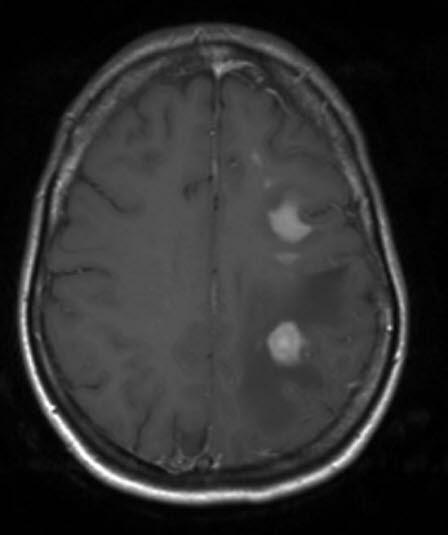

Primært CNS lymfom, aksialt snitt

Gjengitt med tillatelse av Radiologisk avdeling, Universitetssykehuset Nord-Norge